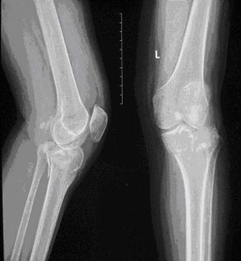

为了防止对胫骨平台骨折手术后延迟负重导致的骨折延迟愈合、关节僵直、肌肉萎缩、骨质疏松等并发症。我们在临床应用气压减重训练仪,采取早期个性化定量的减重负重训练治疗累及关节面的胫骨平台骨折。通过治疗取得良好疗效,患者的骨折愈合良好而没有出现关节面的塌陷,关节功能恢复正常(图1-3)。

图1.一例左膝胫骨平台骨折 图2.内固定术后的X线片表现